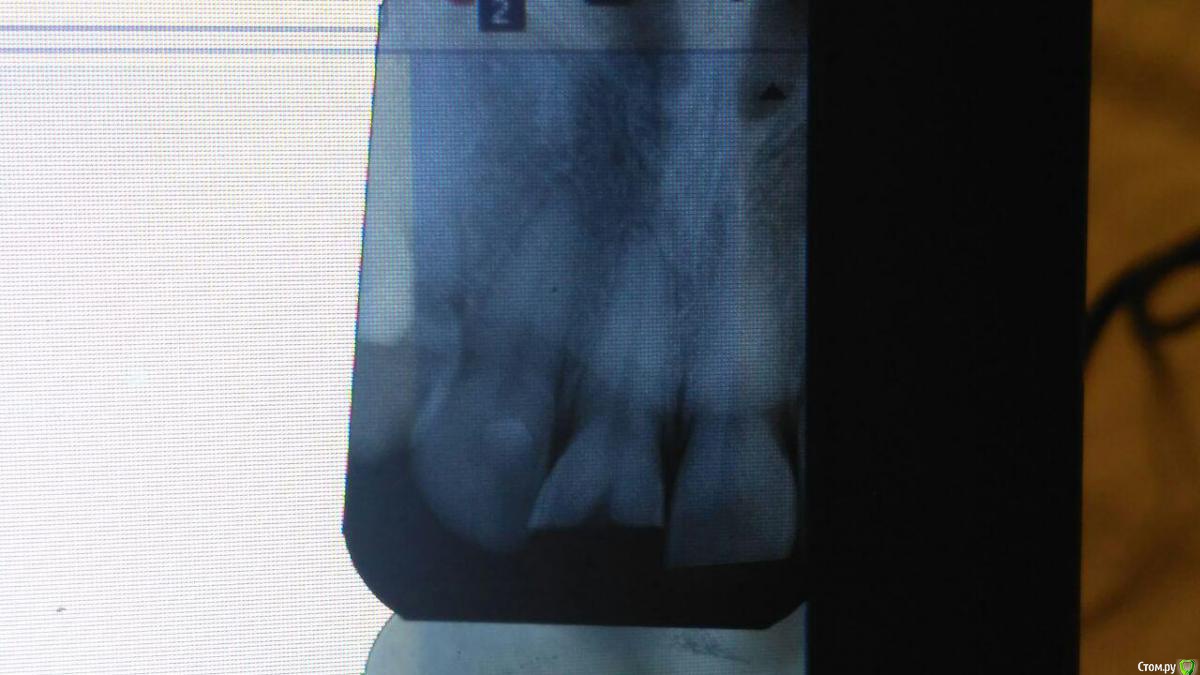

golneva Опубликовано 24 апреля, 2018 Поделиться Опубликовано 24 апреля, 2018 (изменено) Добрый день. Около трех месяцев назад не вписалась в дверной проем с утра и сломала передний верхний зуб. Пол зуба просто откололась. Сразу же обратилась к врачу (врач из очень опытных, наверное больше 30 лет стажа, посоветовали блин). Удалил нерв, залепил "лекарство" через три дня запломбировал канал. Из вариантов лечения предложил только одеть металлокерамику и все. Согласилась потому что никогда не сталкивалась с протезированием, думала что лет до 35 все будет ок, мне 22 года, только 2 пломбы в зубах. После установку вкладки ( хотя это трудно назвать вкладкой) зуб начал болеть, болел очень сильно, врач выписал антибиотики, очень сильный препарат с кучей побочных эффектов, которые я ощутила неподетски, зуб стал болеть чуть меньше и он решил что можно обточить, наколол анестезию такую что в глазах двоилось, но во время обточки он не использовал ни воду, ни десну не защитил и больно было так как будто он меня по живому режет. Прописал другой антибиотик и хлористый кальций, через неделю закончил с обтачиванием, зуб практически не болел. После обтачивания боль слегка усилилась, но когда нужно было одеть коронку он уже почти не болел. Коронка не подошла идеально и врач снова решил обтачивать зуб, и снова было дико больно даже с сильной анестезией. Я говорила что мне больно, врач говорил что я ему вру. Когда я уже не могла терпеть он просто вручил мне в руку коронку и выпроводил. Вся эта канитель длилась чуть больше месяца. В тот же день я пошла к другому врачу, мне сразу сделали снимок где видно что у мня не допломбирован канал, вкладка это просто кусок железки, и между вкладкой и пломбой в канале пустота. На следующий день сделала КТ по совету доктора, он думал что треснул корень. Корень был целым. Доктор достал вкладку (доставал 3 часа), неделю я ходила с "лекарством" с йодом, потом дней 10 с кальцием, канал запломбировали недели три назад. Перед пломбирование зуб не болел совсем. Хожу с временной коронкой, он не болел ни при накусывании, ни при постукивании. Запломбировали хорошо и корень целый. После пломбировки зуб был чувствительным, через неделю был назначен прием чтобы сделать слепок для вкладки, но зуб побаливал и ничего не делали. Доктор сказал подождать надо. Сейчас после пломбирования (прошло уже 3 недели) зуб побаливает при накусывании, при постукивании, даже если прижать его губой он побаливает. Но боль странная, не ноющая как была раньше, а похоже на укол. Ка будто сильнейшая чувствительность, эту ощущение в последние сутки все время, как будто ем лед. если оценить по десяти бальной шкале то это где-то от единицы до трех.может кто-то сталкивался с таким, я не знаю что делать. Есть снимки только сразу после удаления нерва и через месяц после этого. Срезы КТ прилагаю, но только сбоку. Остальные снимки в клинике. Что это просто чувствительность, авитаминоз, фантомные боли??SLX+002.BMP Изменено 24 апреля, 2018 пользователем golneva Ссылка на комментарий

golneva Опубликовано 25 апреля, 2018 Автор Поделиться Опубликовано 25 апреля, 2018 меня смущает темнота на верхушке корня левой единички. Или так и должно быть? Спасибо всем участникам за ответы. Ссылка на комментарий

golneva Опубликовано 25 апреля, 2018 Автор Поделиться Опубликовано 25 апреля, 2018 (изменено) прилагаю еще две ссылки на скиншот это кт 1,5 месяца назад с вкладкой и проблемным каналом https://pp.userapi.com/c846019/v846019009/31dd8/jYA-TT3sZI4.jpgэто сегодня без вкладки с перелеченым каналом fhttps://pp.userapi.com/c846019/v846019009/31de2/cRZp8W0TM2E.jpg Изменено 25 апреля, 2018 пользователем golneva Ссылка на комментарий